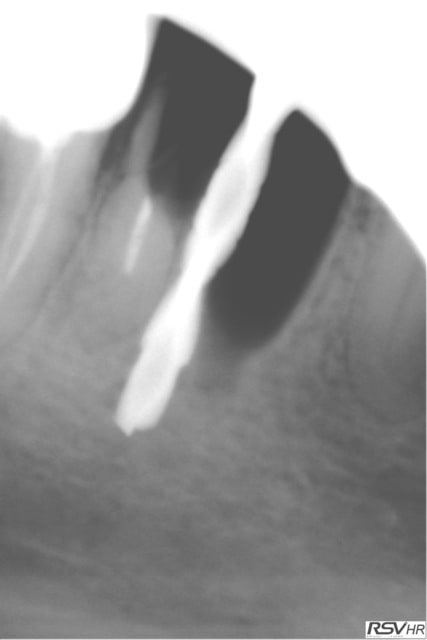

même si je me redirige plutôt vers Zimmer avec une insertion primaire supérieur (à mon avis ) voici un cas de plusieurs années

j'avais gardé une racine distale de 46 (montage 2 ccm soudées au début 4647- avec diastème avec 45 ;2008;le montage

n'a pas tenu longtemps=extraction racine distale et

implantation immédiate legacy2 7 mm(2011)

et ccm transvissée 3 mois après

radio à 2015